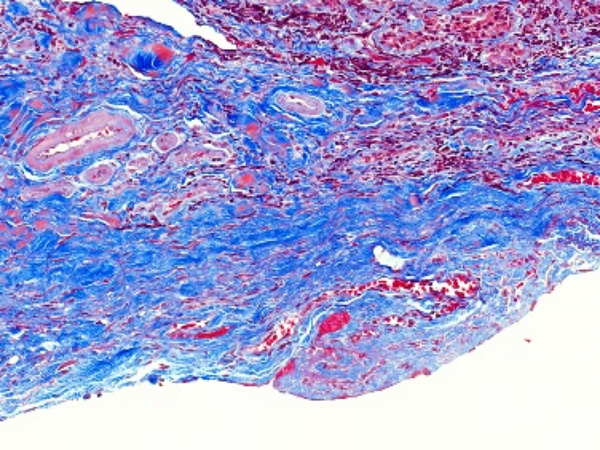

特殊染色是病理学和组织学中使用的一种染色方法,用于显示组织或细胞中的特定成分,这些成分在常规的苏木精 - 伊红(HE)染色中可能无法清晰地显示。以下是关于特殊染色的详细介绍:**一、常见的特殊染色方法及原理**1. 网状纤维染色 - 原理:网状纤维主要成分是Ⅲ型胶原蛋白,其表面有糖蛋白,具有

400-6863-680 立即咨询特殊染色是病理学和组织学中使用的一种染色方法,用于显示组织或细胞中的特定成分,这些成分在常规的苏木精 - 伊红(HE)染色中可能无法清晰地显示。以下是关于特殊染色的详细介绍:

**一、常见的特殊染色方法及原理**

1. 网状纤维染色

- 原理:网状纤维主要成分是Ⅲ型胶原蛋白,其表面有糖蛋白,具有嗜银性。常用的染色方法是银染法,例如Gomori法。在这个方法中,通过氨银溶液处理组织切片,银离子会被网状纤维吸附,然后经过还原反应,使银离子还原为金属银,沉积在网状纤维上,使其呈现黑色。这种染色对于显示肝脏、脾脏等组织中的网状支架结构非常有效。

2. 网状纤维染色

- 网状纤维呈黑色。在肝脏中,网状纤维围绕在肝细胞索周围,形成肝脏的支架结构;在脾脏的白髓和红髓交界处,也可以清晰地看到网状纤维的分布。这种染色对于判断肝脏纤维化程度、脾脏组织结构等有重要意义。